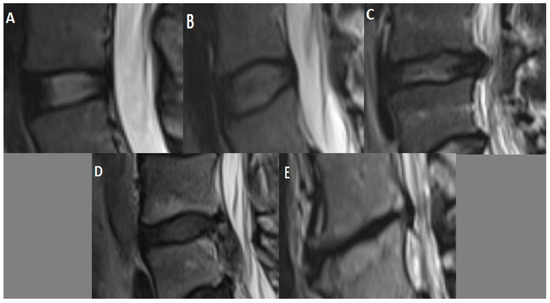

At the L4–L5 intervertebral disc level, measurements with sagittal T2-weighted MRI sequence and Pfirmann grading [15] for disc degeneration were performed (Figure 2). Disc pathologies were classified with axial T2-weighted MRI sequence. The Pfirrmann grading system is divided into five categories. It is accepted as a reliable method for classifying disc degeneration in MRI scans utilizing parameters such as disc structure, height, signal qualities, and nucleus and annulus differentiation [15,17].

Figure 2.

Pfirrmann grading scale for intervertebral disc degeneration with sagittal T2-weighted MRI sequence: Grade I (A)—homogeneous white normal disc; Grade II (B)—inhomogeneous white disc, normal disc height, may have horizontal bands; Grade III (C)—inhomogeneous gray disc, slightly reduced disc height; Grade IV (D)—inhomogeneous black disc with no clear distinction between the annulus and nucleus, marked loss of height in the disc; Grade V (E)—inhomogeneous black collapsed disc.